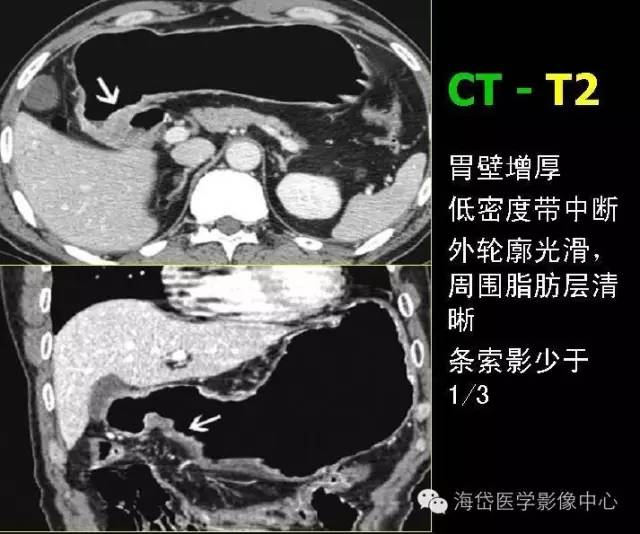

T2:胃壁增厚,低密度帶中斷,外輪廓光滑,周圍脂肪層清晰條索影少于1/3